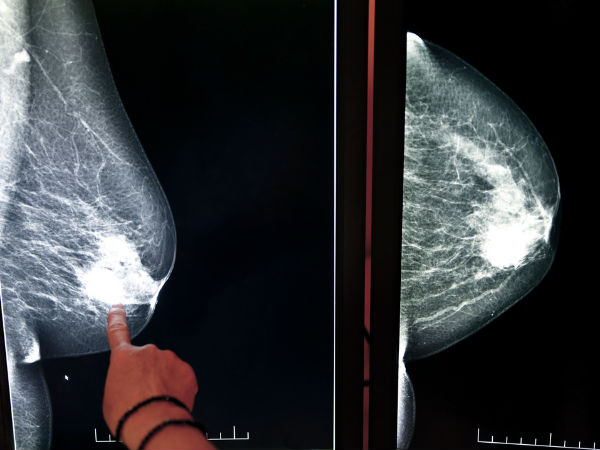

மார்பக புற்றுநோய்

மிகவும் சிறிய அளவிலான பிராவை ஒரு பெண் தேர்ந்தெடுத்து அணிவதைத் தவிர்க்க வேண்டும். முக்கியமாக இந்த விஷயத்தில் எச்சரிக்கையாக இருக்க வேண்டும். ஏனெனில் சிறிய அளவிலான பிரா மார்பக பகுதிகளில் இரத்த ஓட்டத்தைத் தடுத்து, மார்பக புற்றுநோய்க்கு வழிவகுக்கும். இது ஒரு பொதுவான பக்க விளைவாக இல்லாவிட்டாலும், சில பெண்களுக்கு மார்பக புற்றுநோய் வருவதற்கு இதுவும் ஒரு காரணமாக உள்ளது. எனவே எச்சரிக்கையாக இருங்கள்.